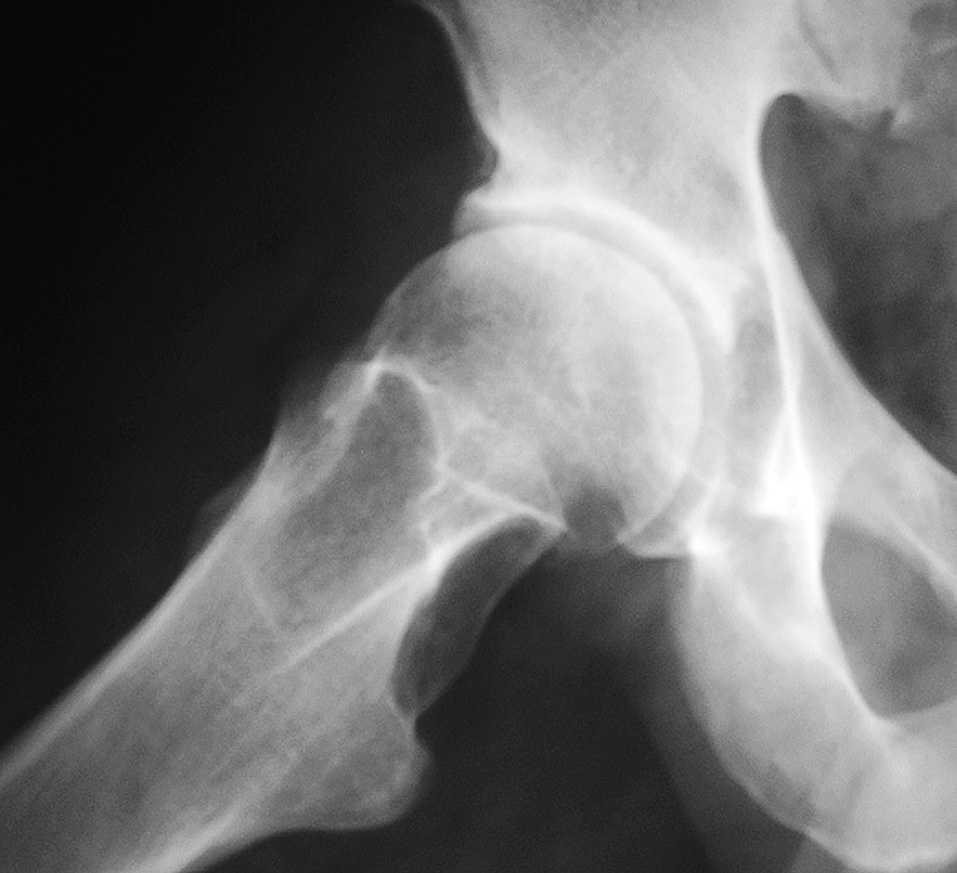

Fig. 2. Radiografía de cadera derecha axial. Pérdida de convexidad en la interfaz cabeza-cuello de cadera derecha (signo de la giba o pistol grip).

El AFA es el resultado del choque de la interfaz cuello-cabeza femoral contra el reborde acetabular anterior, al realizar un movimiento de flexión y aproximación1. Se han descrito 2 mecanismos patológicos: efecto "cam"2 y el efecto "pinza"3, que responden a 2 alteraciones anatómicas, como son la pérdida de la concavidad de la interfaz cabeza cuello y la retroversión acetabular, respectivamente. En la radiología se pueden observar 2 signos característicos: el signo de la giba y el signo de lazo. También podemos encontrar imágenes que corresponden a lesiones subcondrales quísticas4. El tratamiento de estos pacientes incluye desde antiinflamatorios no esteroideos hasta osteotomías pélvicas5.